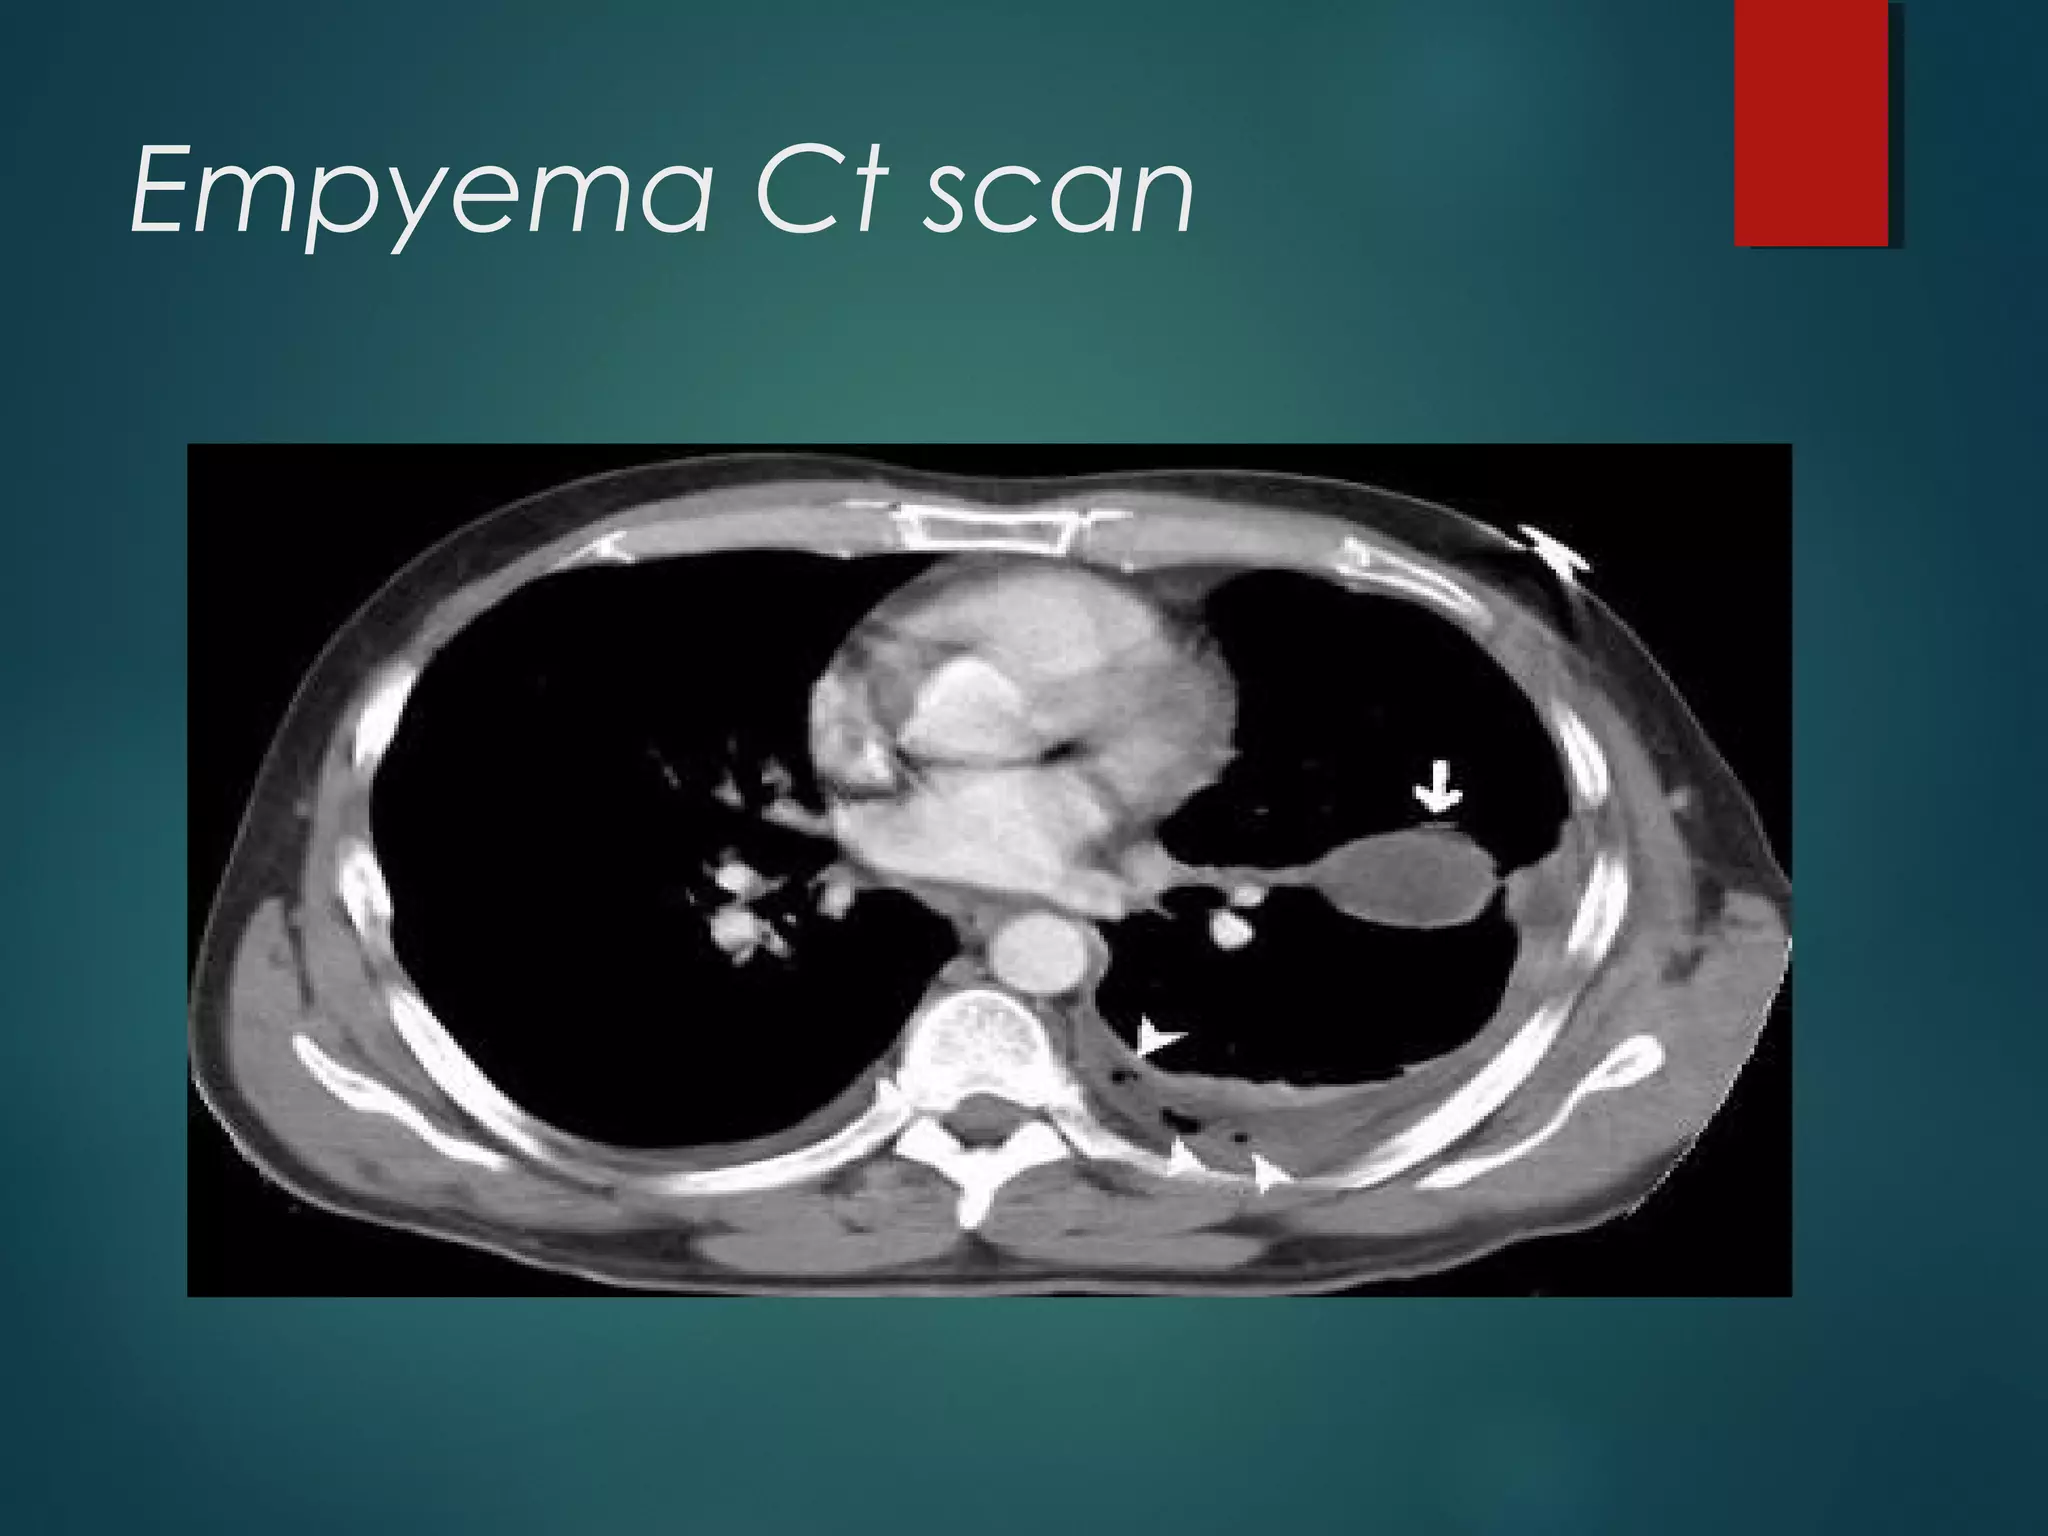

Empyema Ct scan

empyema